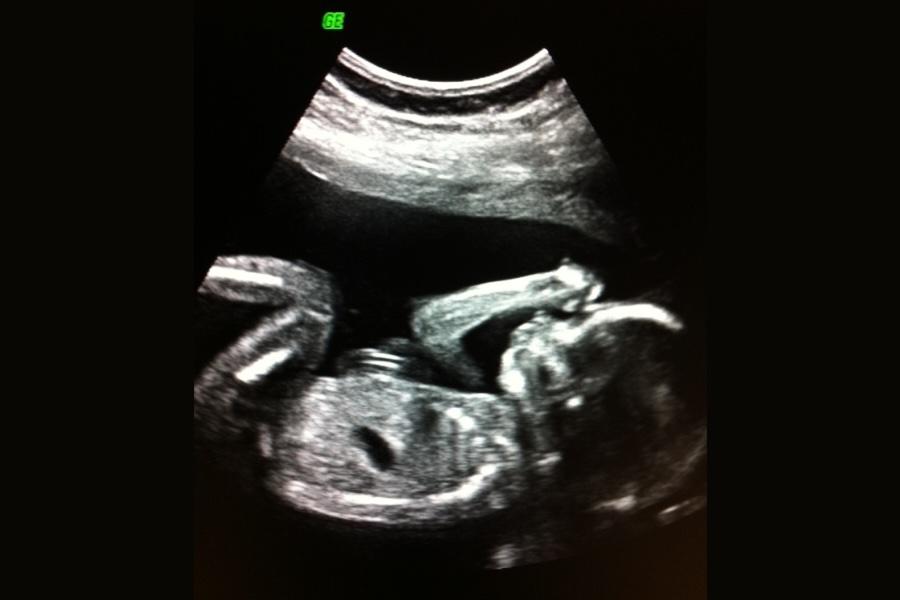

De allra flesta som väntar barn i Sverige gör någon typ av fosterdiagnostik. RUL – eller rutinultraljud – är en ultraljudsundersökning som görs mellan graviditetsvecka 18–20.

Den här undersökningen syftar till att se hur många foster du bär på och vilken placering moderkakan har. I vissa fall dateras även graviditeten, om det inte gjorts innan. Det är framförallt en genomgång av barnets anatomi som sker, alltså att man går igenom barnets kropp med ultraljud och ser på alla organ så noggrant man kan. Alla sjukdomar eller avvikelser kan inte upptäckas vid ett rutinultraljud.